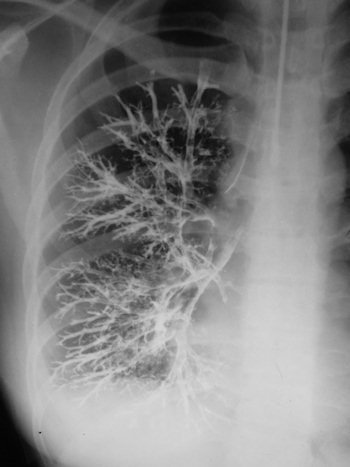

Bronchography

In bronchography, the bronchial tree was opacified with an opaque medium using a variety of techniques. In the illustration below, a catheter was used with contrast injected. The examination shows a normal right bronchogram. The examination was unpleasant for the patient, and there was therefore a high threshold of referral for performing the examination. The chest physician would be reluctant to submit the patient for the procedure unless there was a degree of confidence about the examination.

The introduction of high-resolution CT (HRCT) has considerably changed attitudes about bronchiectasis. Because so many more patients are examined than were possible with bronchography, it is now known that bronchiectasis is much more common than physicians had previously appreciated. The first experimental bronchogram was performed by Karl Springer from Prague in 1906, which is surprisingly early. Over the years, the technique used many contrast agents, including colloidal silver and bismuth. In classical brochography, iodized oil was used, commonly introduced by tracheal injection. Contrast could also be introduced using a catheter, bronchoscope, or dripped over the back of the tongue.